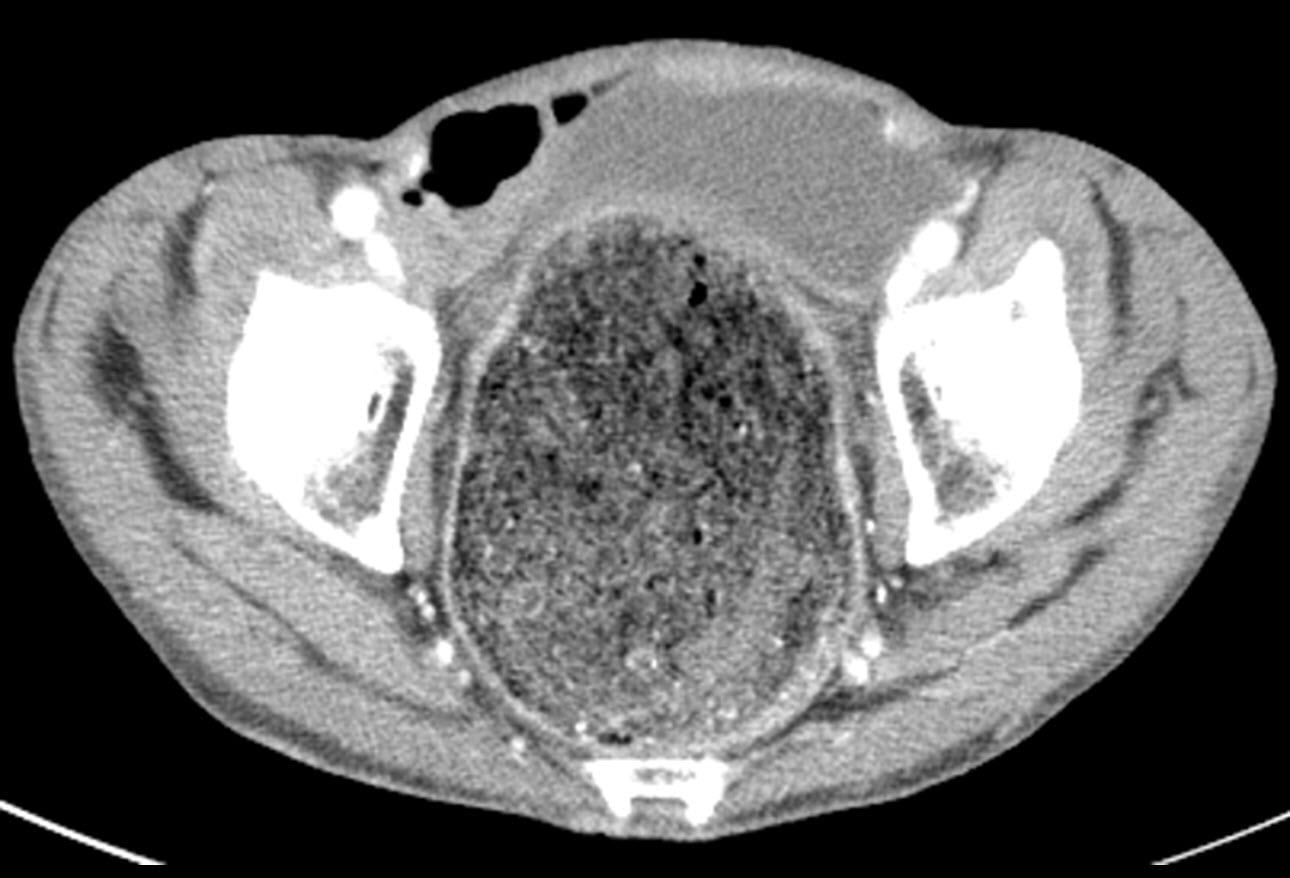

from www.cmaj.ca

Ogilvie syndrome acute pseudoobstruction of the colon CMAJ